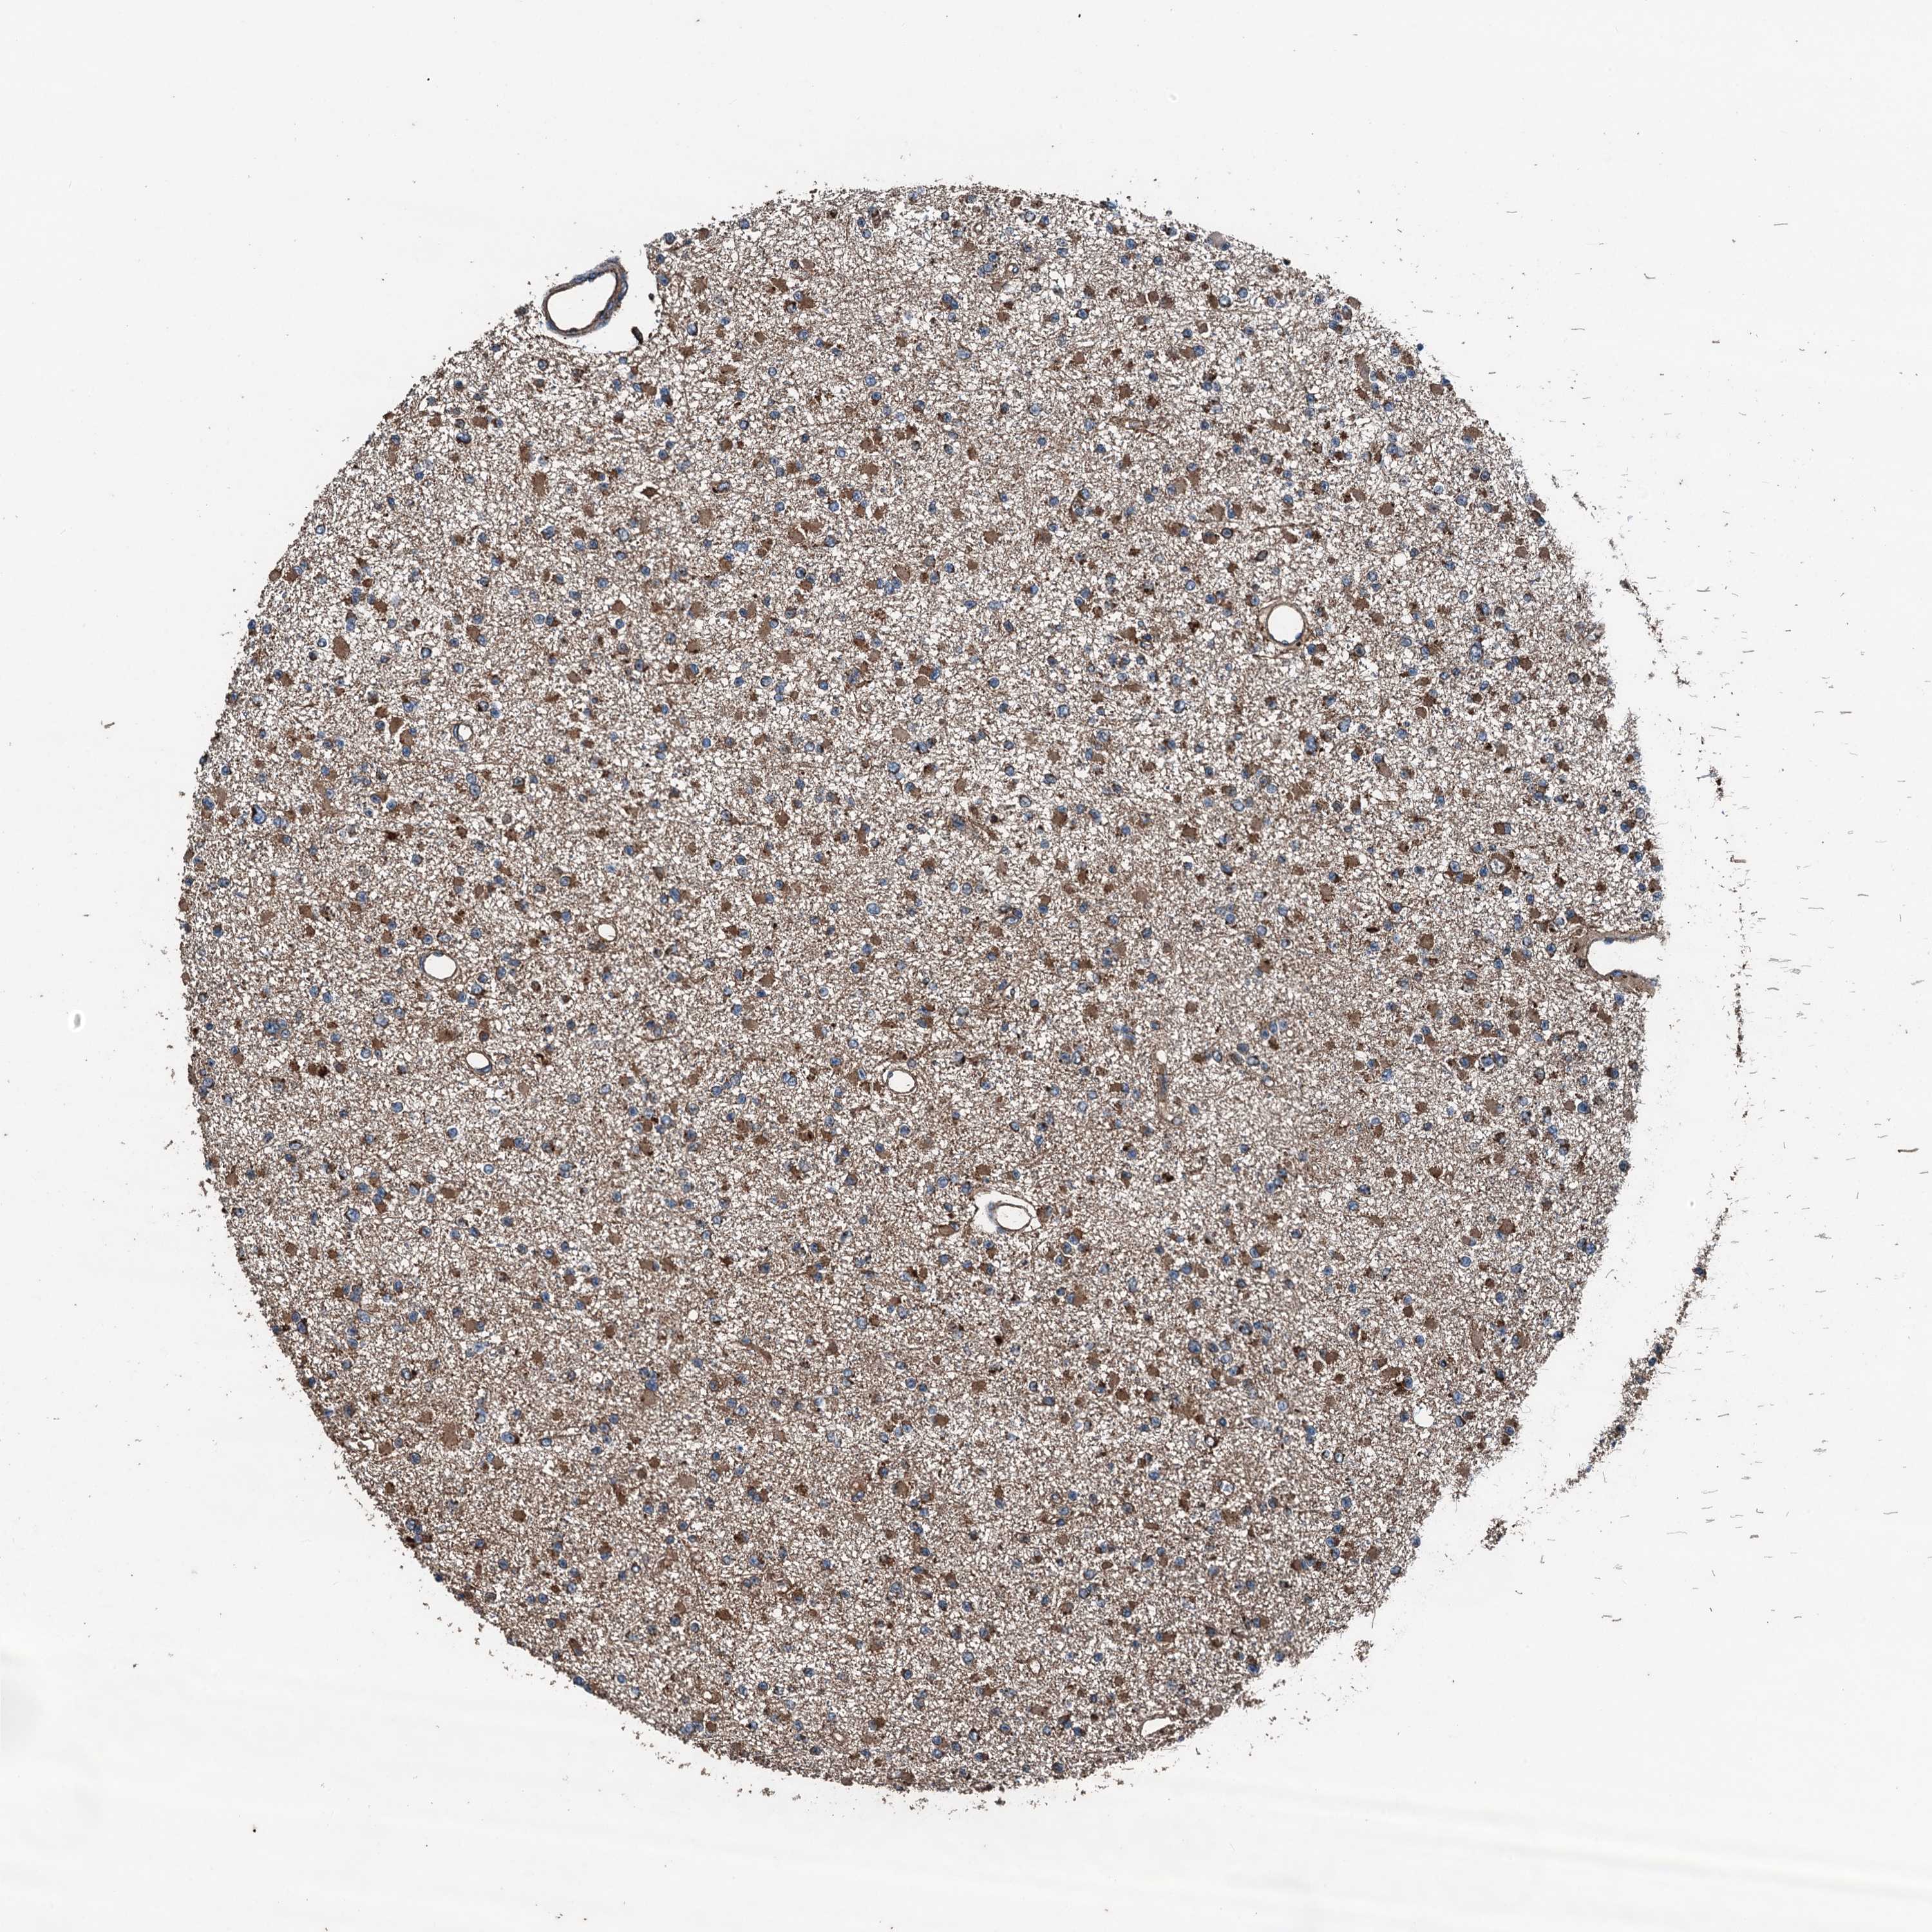

GLIOMA - Protein expressioni

A mouse-over function shows sample information and annotation data. Click on an image to view it in a full screen mode. Samples can be filtered based on level of antibody staining by selecting one or several of the following categories: high, medium, low and not detected. The assay and annotation is described here.

Note that samples used for immunohistochemistry by the Human Protein Atlas do not correspond to samples in the TCGA dataset.

Antibody stainingi

Antibody staining in the annotated cell types in the current human tissue is reported as not detected, low, medium, or high, based on conventional immunohistochemistry profiling in selected tissues. This score is based on the combination of the staining intensity and fraction of stained cells.

Each image is clickable and will lead to virtual microscopy that enables deeper exploration of all samples and also displays staining intensity scores, fraction scores and subcellular localization as well as patient and tissue information for each sample.

Antibody HPA041227

Staining

High

Medium

Low

Not detected

Intensity

Strong

Moderate

Weak

Negative

Quantity

>75%

75%-25%

<25%

None

Location

Nuclear

Cytoplasmic/membranous

Cytoplasmic/membranous,nuclear

Glioma, malignant, High grade

Glioma, malignant, Low grade